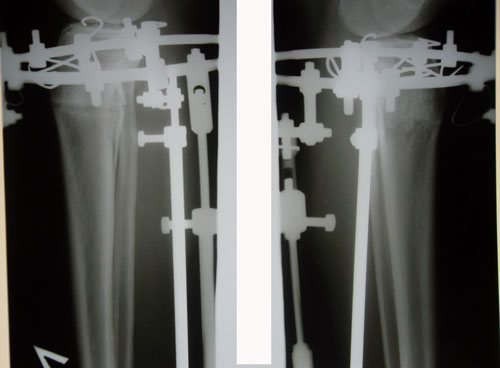

- Диагноз: О-образная деформация ног

Розочка, привет!!!!!!!! Ножки супер, ооочень красивые